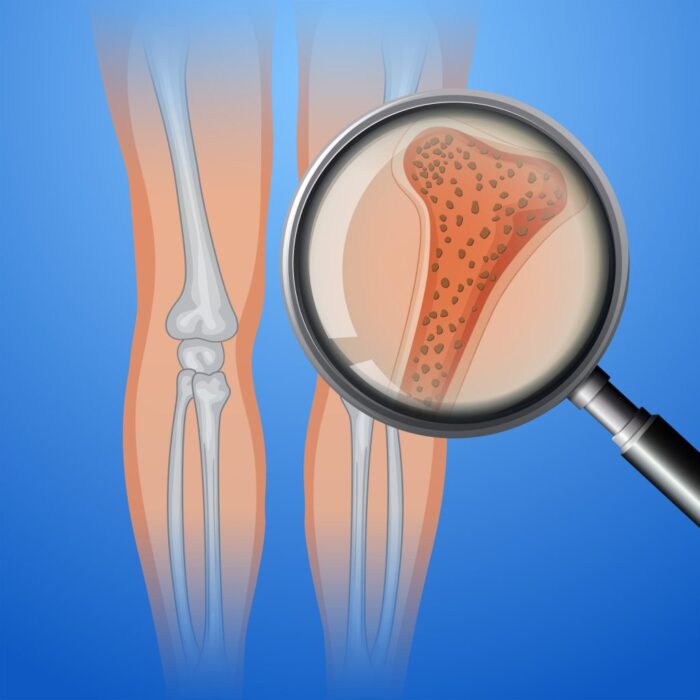

Herbs for increasing bone density. Many women undergo periodic examinations such as the Pap test or mammography, but they often overlook another equally important test: bone density determination.

Certain women are at an increased risk of losing bone mass, a condition known as osteoporosis, where bones are at a higher risk of fracture.

Factors that increase the risk of osteoporosis include: